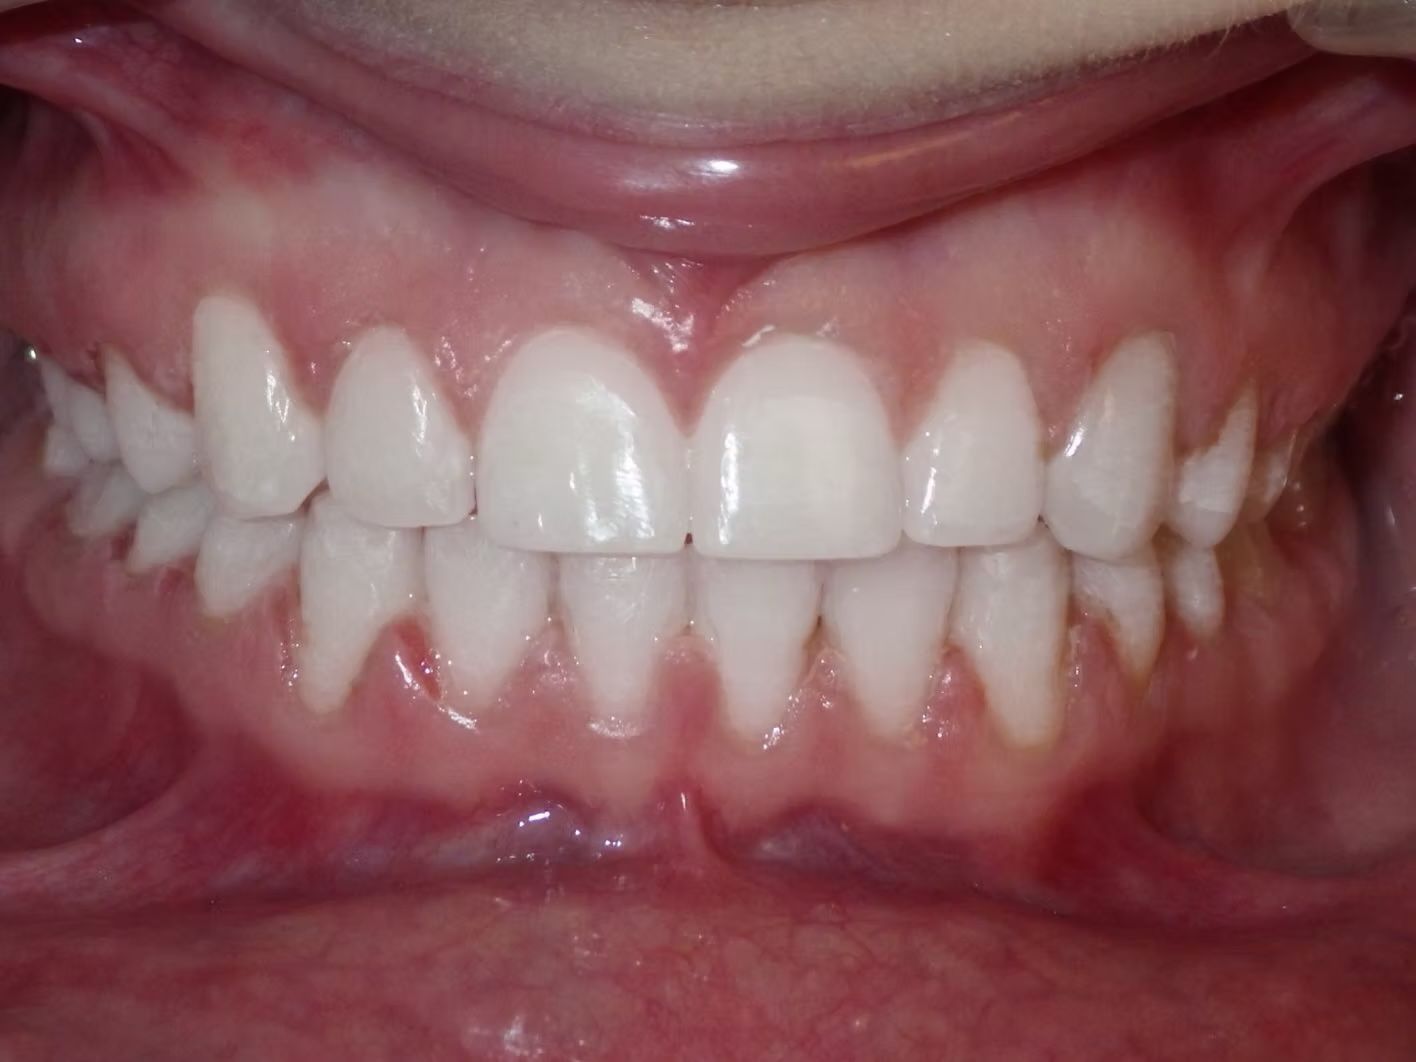

AMBER

Amber, began treatment with Dr. Bret because she didn't like that her front teeth overlapped each other. She had narrow top and bottom dental arches with severe crowding of her upper and lower teeth. She was treated with braces on the upper and lower teeth, and we used the braces to widen the smile. What a change!